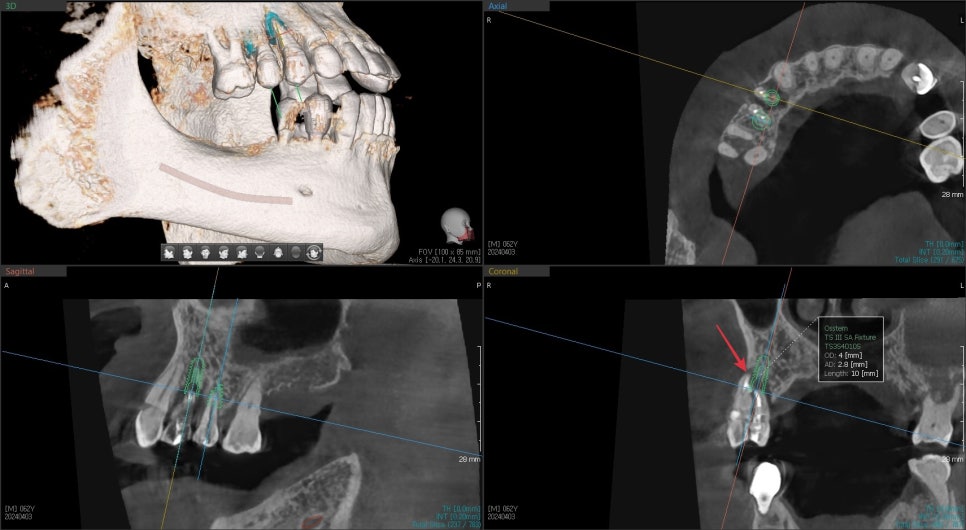

발치 후 임플란트 즉시 식립을 해야 하지만

화살표로 표시된 부분이 염증으로 인해 흡수되어

임플란트를 식립하더라도 주변 뼈가 없어

노출이 될 수밖에 없는 상태였습니다.

다행히 수술 약 4개월 후 3D CT에서

임플란트 주변으로 흰색으로 보이는 뼈가 생성된 것을 확인할 수 있었습니다.

역시 초진 3D CT에서 치아를 감싸는 한쪽 벽을 이루는 뼈가 흡수되어

치아 뿌리가 노출된 상태에서 이 역시 발치 후 즉시 임플란트 식립 시

기존 잇몸을 차폐막으로 이용하여 치조골 이식술을 동반했습니다.

수술 후 4달 후 사진입니다.

임플란트 주변에 흰색 뼈가 생성된 것을 볼 수 있었습니다.